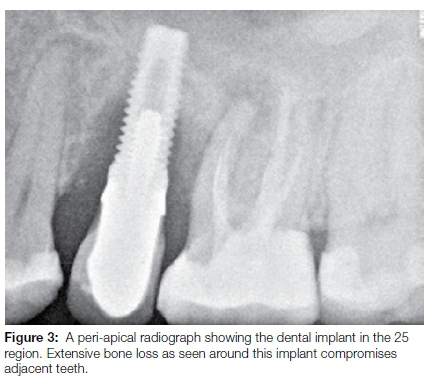

Peri-implantitis lesions are often larger in size and occupy a much greater surface area. These lesions may extend to a position apical to the pocket epithelium, while not being surrounded by non-infiltrated connective tissue as seen in periodontitis lesions. Increased numbers of pathogenic bacteria and a decreased immune response due to anatomical differences between implants and teeth may contribute to a more aggressive and progressive tissue destruction process around implants (Figure 3).26,27 Therefore, assumptions that disease within periodontal tissues and peri-implant tissues behave in a similar way regarding etiopathogenesis, diagnosis, classification and treatment, cannot be made.28,29